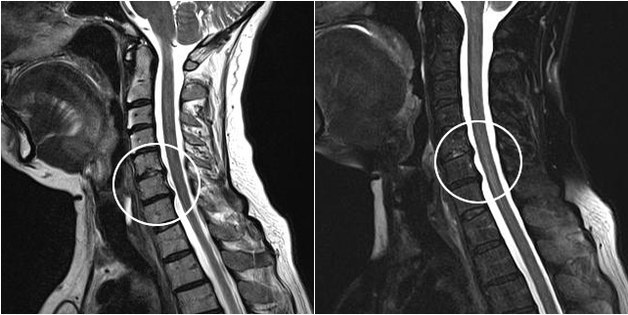

I moderni metodi diagnostici includono la risonanza magnetica e la TC, che consentono di studiare in modo più accurato i processi di distruzione della cartilagine e del tessuto osseo. Questa tecnica può essere utilizzata anche per diagnosticare comodamente ernie e altri difetti dei tessuti molli vicino alla fonte della malattia.